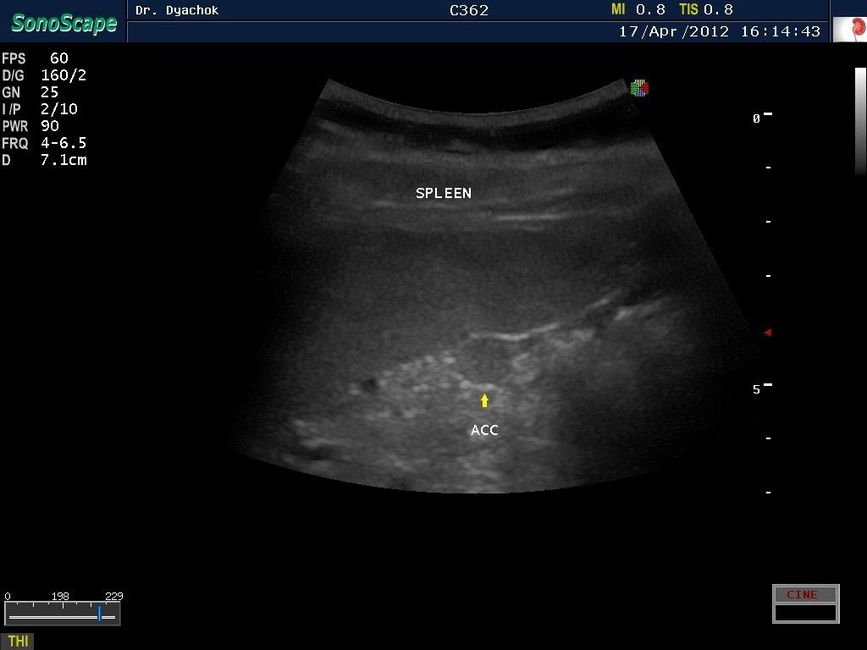

• Исследования поверхностных и абдоминальных органов